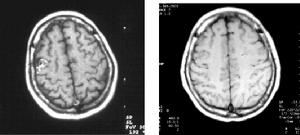

2.CT 松果體細胞瘤多呈邊界清楚的類圓形病灶,等或等高混雜密度有散在的鈣化,發生室管膜下轉移時可見腦室周圍帶狀略高密度的病灶。生殖細胞瘤邊界不規則,有時呈蝴蝶狀,多有彈丸狀鈣化,有的可見側腦室內播散,可以此確診,如圖2所示。畸胎瘤含有脂肪、骨骼及牙齒故多呈混雜密度,有低於腦脊液密度的脂肪密度區和接近骨質密度的高密度區。MRI:對腫瘤的周圍結構顯示較好,有信號不均及強化明顯的特徵(圖3)。